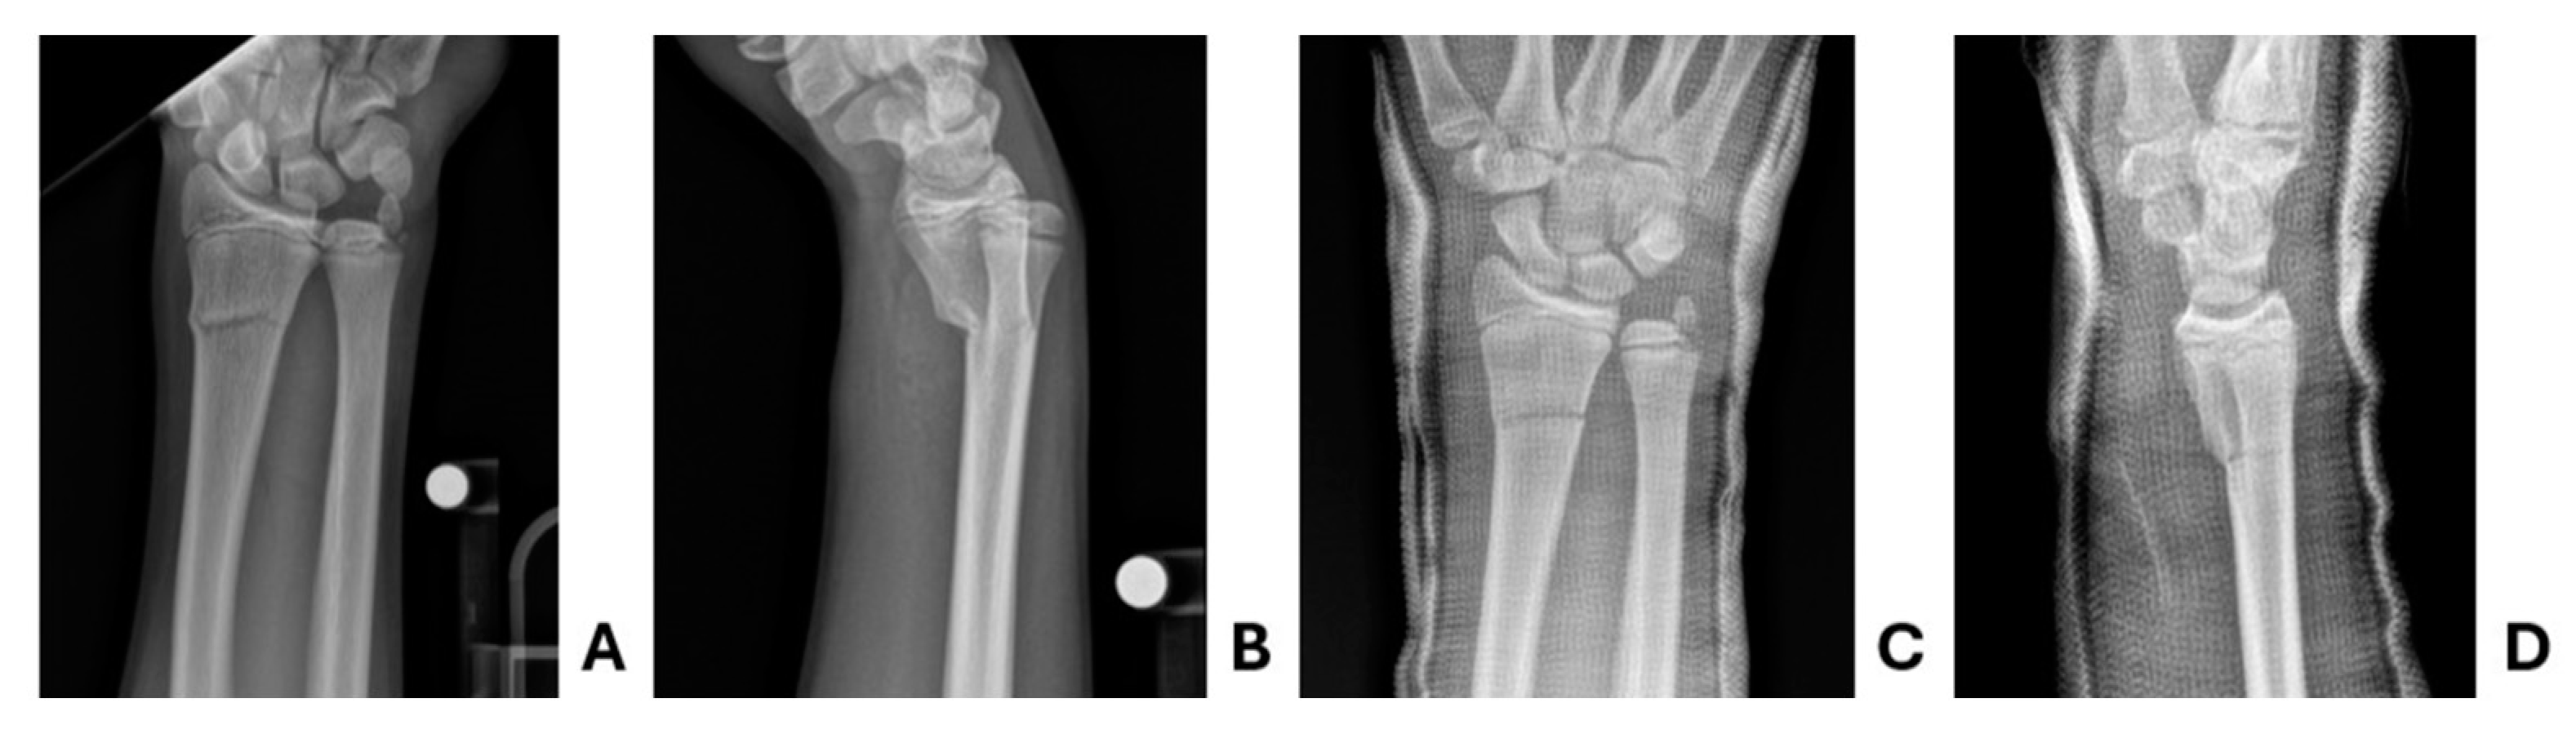

Figure 6. Patient three pre- and post-reduction radiographs. Pre-reduction A anteroposterior and B lateral radiographs demonstrating acute distal radius and ulna fracture. Same day post-reduction C anteroposterior and D lateral radiographs demonstrate stable interval reduction.

3.3. Patient Three

14-year-old male presented to the ED with right wrist pain following an injury sustained at hockey practice when he was checked into the boards. He did not sustain any head trauma or any other injuries at that time. In the ED, the patient was noted to have an obvious deformity of the right upper extremity with tenderness overlying the wrist. He was neurovascularly intact. X-ray of the right radius and ulna were notable for a distal radius fracture, >20 degrees of angulation (Figure 6). Orthopedics was consulted and recommended non-operative management with closed reduction and casting. Procedural sedation was the initial method discussed with his family, though his family continued to feel uncomfortable with the potential risks of complication and need for monitoring. Supraclavicular block was performed to facilitate bedside reduction and long arm casting. He was subsequently followed at an outside Sports Medicine facility, locally. X-rays obtained during follow-up 10 days and 27 days later demonstrated appropriate alignment and robust healing response, respectively. He was felt to make a complete clinical recovery from his distal radius and ulna fractures and encouraged to follow-up on an as-needed basis.